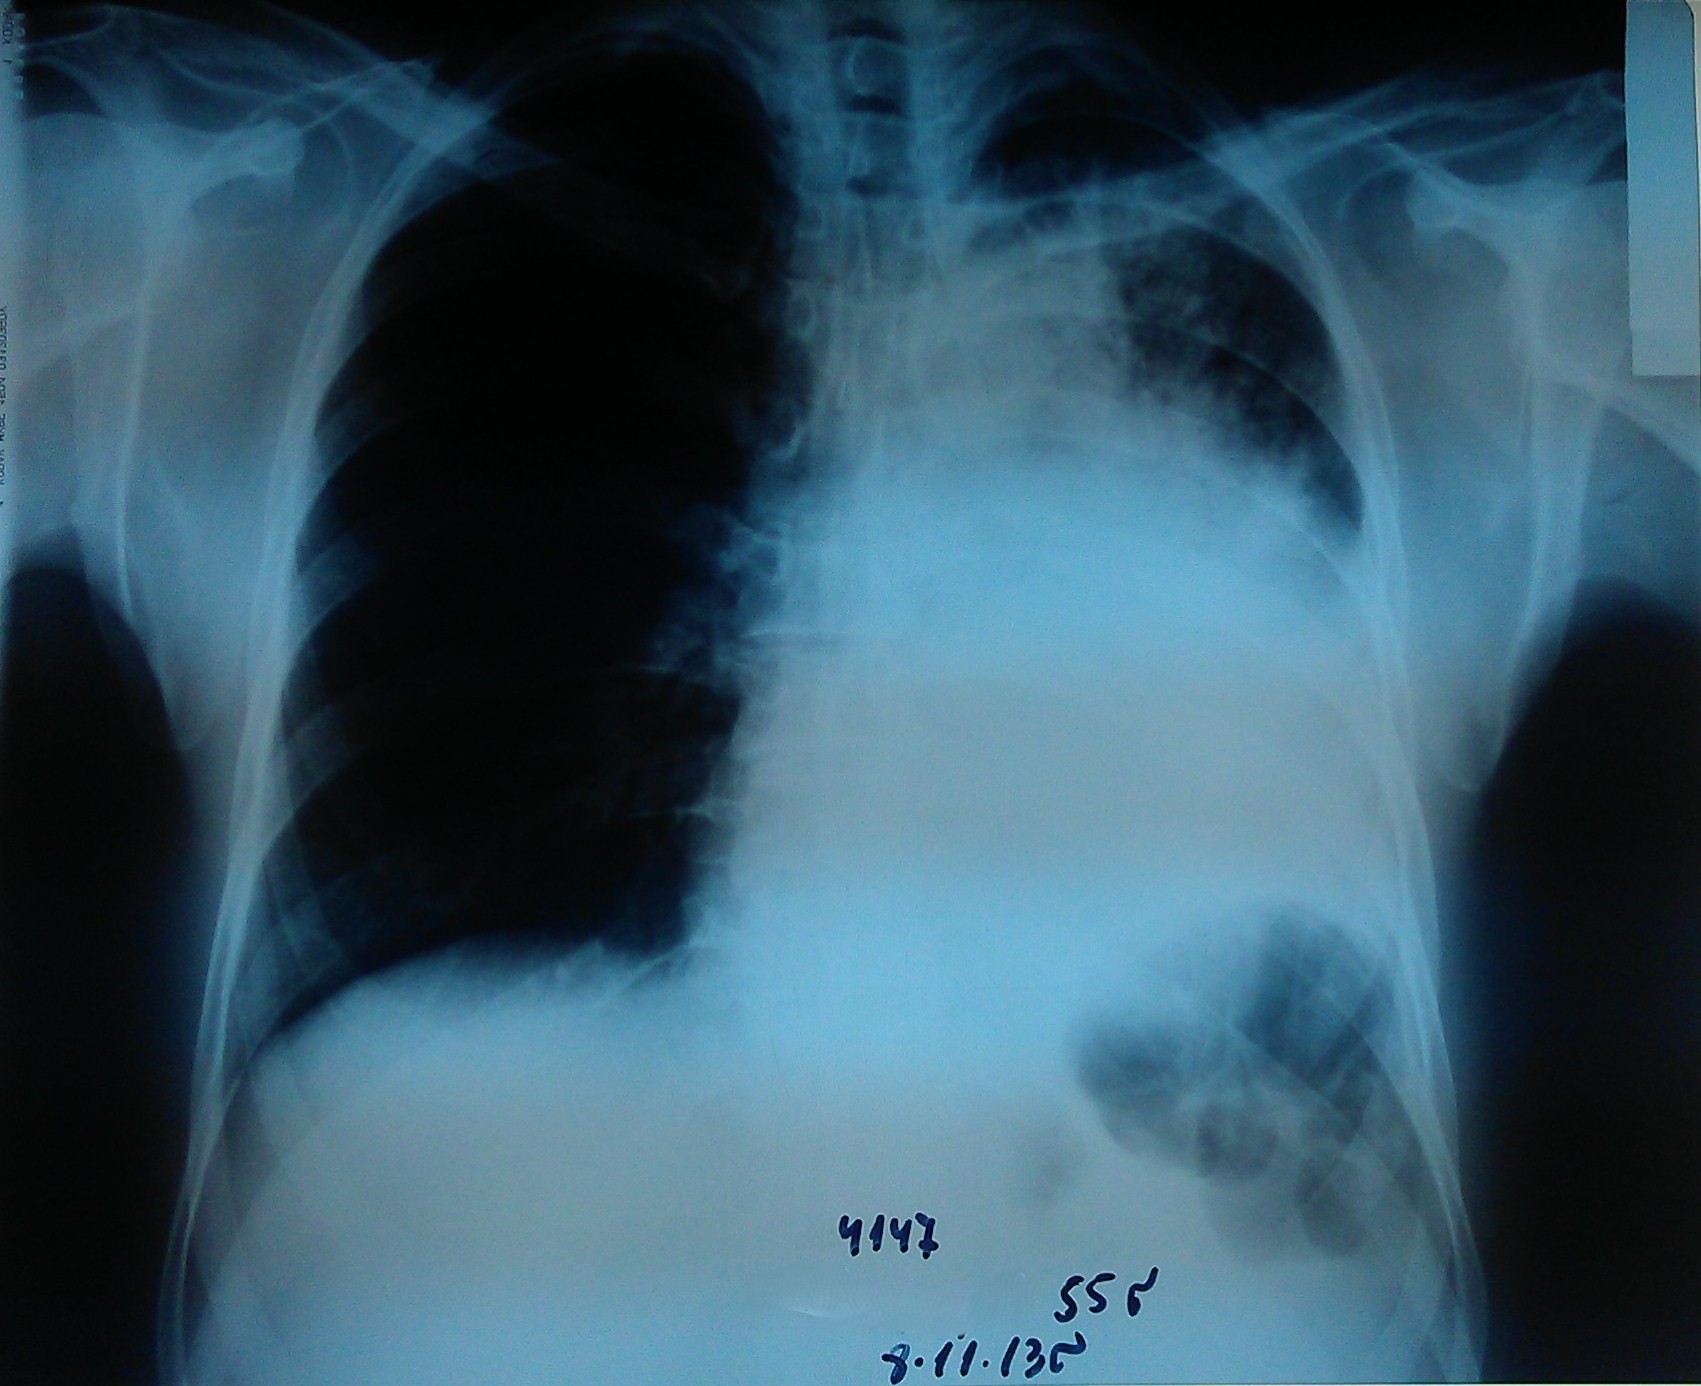

- გულმკერდის რენტგენოგრაფია რეზექციამდე 1 კვირით ადრე

აღინიშნება მარცხენა ფილტვის თითქმის სრული ატელექტაზი.